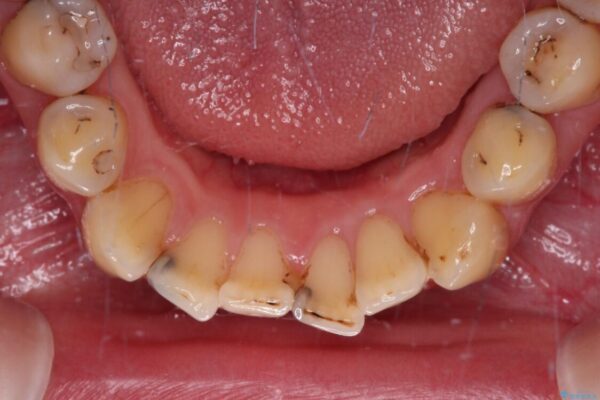

治療前

• むし歯だらけの前歯をオールセラミッククラウンできれいに 治療前画像

上下前歯や奥歯の虫歯治療を希望して来院された患者様です。

全顎的にむし歯が多く、根管治療の必要な奥歯や、審美的に気になっている前歯を中心にオールセラミッククラウンにて補綴治療を行うこととしました。